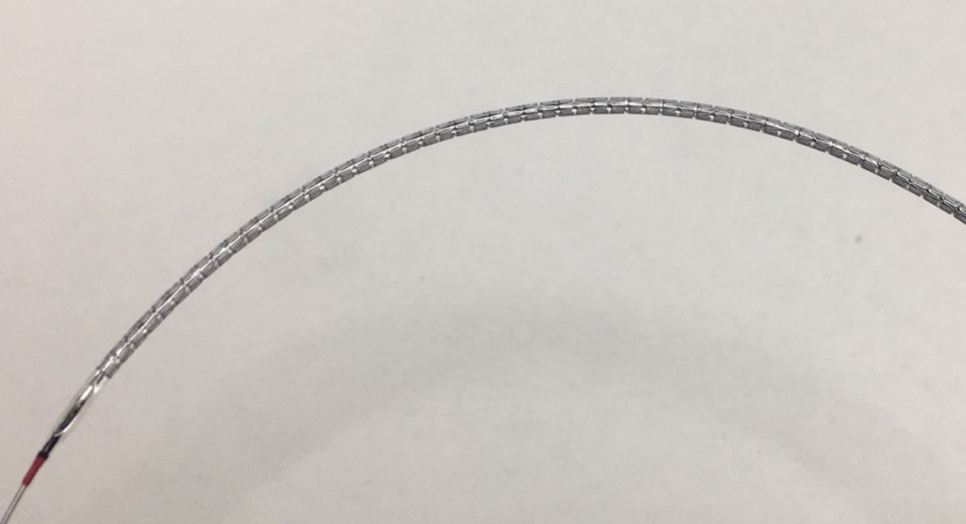

可吸收藥物洗脫支架盡管作為一種重要的研究熱點,但一直沒有很好解決可吸收材料問題。鐵基藥物洗脫可吸收外周支架采用的基材為滲入了0.05%氮的純鐵材料(Fe),所載藥物是西羅莫司。這款可吸收支架的優(yōu)勢包括:獨特的滲氮工藝使這款可吸收支架在維持足夠支撐力的同時支架壁厚可降低到60μm,支架規(guī)格豐富,最長可達118mm,專門為膝下動脈病變開發(fā);該支架通過聚乳酸(PLA)涂層載藥控制藥物釋放,能夠有效地抑制平滑肌細胞的增生和遷移;整個支架的降解周期為18-24個月。該支架是國際唯一的以鐵基為材料的全降解血管支架。